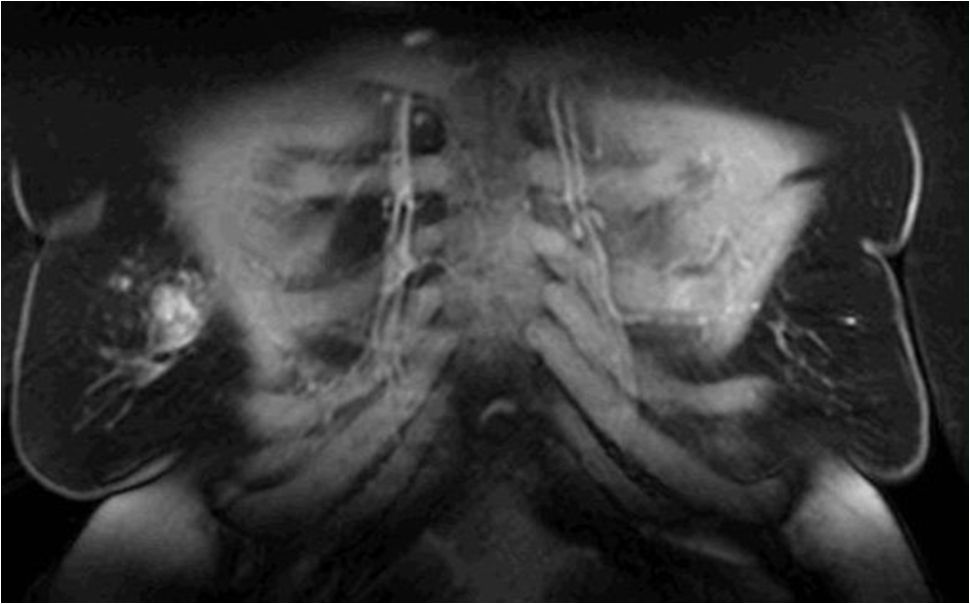

![]() MR, Frontalschnitt mit Darstellung der parasternalen Gefäße (= Mammaria interna). | ||